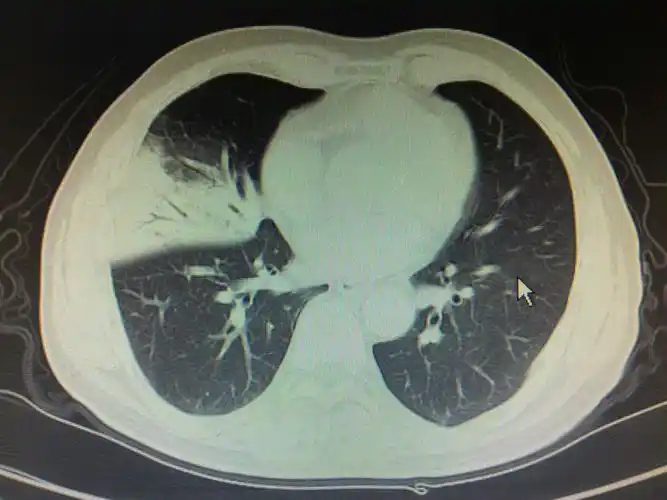

大叶性肺炎一例